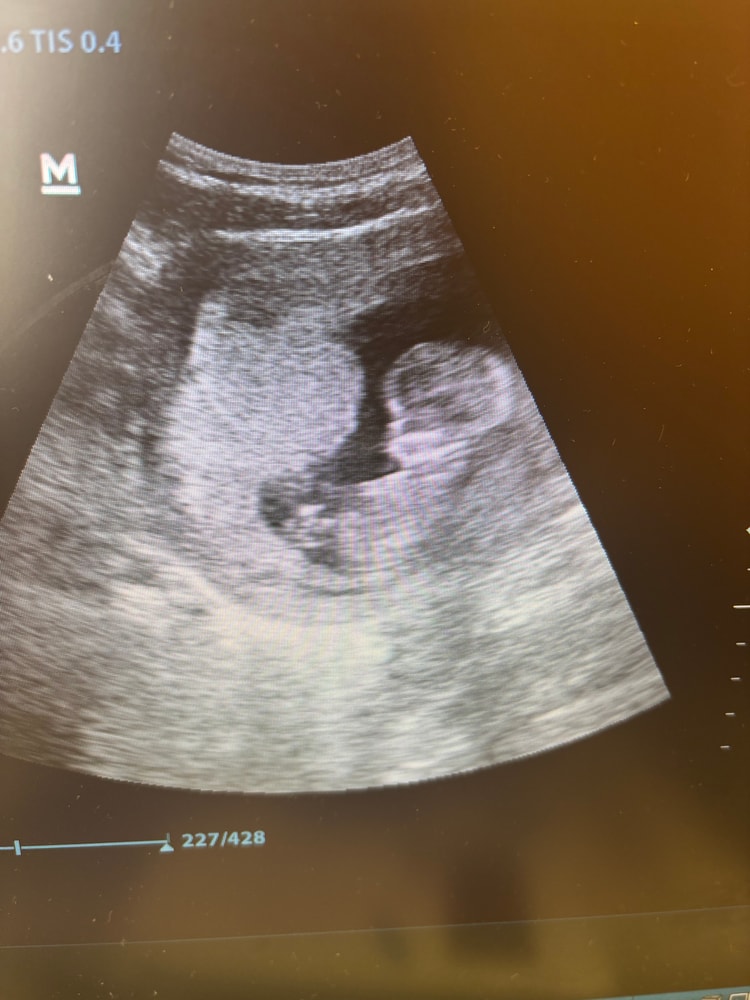

УЗИ, КТГ, доплерДевочки, хотела сразу сюда написать с дублированием в дневник, но почему-то только в дневник отправилось. Была на УЗИ сегодня в ЖК, плановый прием. Показали малыша. Нам сегодня 12/4 недельки. Врач сказала, что все хорошо, малыш согласно сроку развивается. Я потом ехала и смотрю, что у него головешка прям большая. Подскажите, пожалуйста, норм ли для моего срока?

Ээ… ну на вид странно определять, на скринингах замеры делают как раз для этого), но в целом - ребенок не кабачок, растет не равномерно, и на ранних сроках голова у плода всегда больше, потом эта пропорция выровняется.

IMPREGGY, фуф, спасибо, а то я в кабинете внимание не обратила, уже в дороге рассмотрела. Еще и муж отметил, что мегамозг у нас растет)))

Какой хорошенький 🥰 читала, что у них голова больше тела долго, потом выравнивается. А скрининг уже был? Что говорили врачи?

Если очень беспокоитесь, можете сравнить параметр БПР (расстояние от виска до виска) из протокола вашего УЗИ с табличками. Но если врач ничего не сказала про отклонение, но, наверное, всё ок! А по поводу фото - они в принципе все такие, а ваш, кажется, ещё и улёгся так, что голова в фокусе

Candela, да, она не сказала и нигде ничего не записала. На прошлом УЗИ измеряла размер плода именно, так как подтверждали срок. На этом она не предложила его смотреть даже, я попросила, поэтому никаких замеров не было. Я так понимаю, будут на скрининге через неделю. Да, гиня сказала, что все хорошо с малышом, проснулся, мол, шевелюкается там в животике))) ПЯ хорошее сказала и сам малыш в норме. Я не то, чтобы прям очень переживаю, просто уже потом, выйдя от врача обратила внимание на головешку, еще и муж акцент на этом сделал, ну в шутливой форме)))